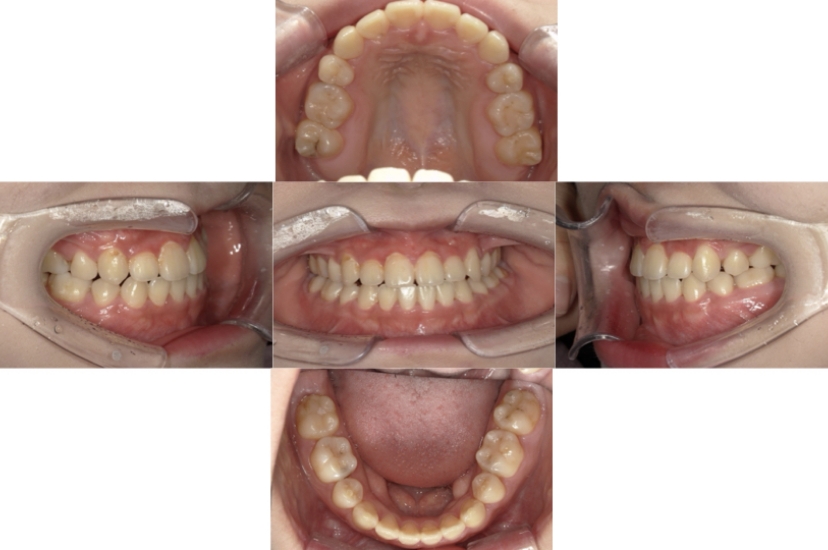

上下顎叢生(上下の前歯のガタガタ)のケースです。

装置はラビアル(上下表側)で、上下顎の小臼歯を4本抜歯を行っています。抜歯したスペースを使って、上下の前歯の後方移動と叢生(ガタガタ)の改善を行っています。

主訴 歯並びが悪く、舌を噛んでしまうのを治したい。

年齢・性別 27歳 男性

お住まいの地域 東京都大田区

治療方針 抜歯スペースを利用して上下前歯の叢生(ガタガタ)の改善

抜歯部位 上下顎左右第一小臼歯

使用装置 ラビアル(上下表側)、顎間ゴム

治療期間 3年1か月

治療回数 30回

AFTER